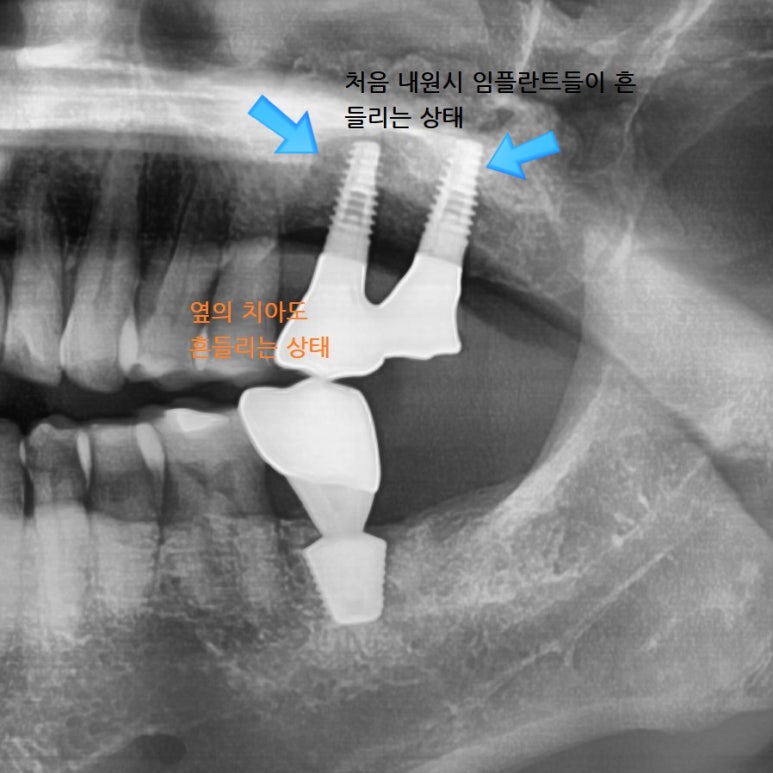

다른치과에서 오래전에 수술한 임플란트가 많이 흔들리고

또한 엑스레이 상에 인프란트 주변 뼈도 많이 녹아있어

묶여있는 임플란트 2개를 제거하였습니다.

두 개 중 하나는 흔들려서 쉽게 제거되었으나 나머지 하나는 상부 뼈가 녹아있음에도

뿌리부분에는 임프란트 픽스쳐가 뼈와 강하게 유착되어 있어 다 갈아내어 임플란트를 제거하였습니다.